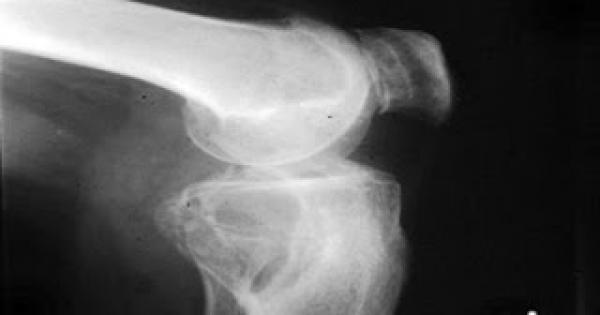

يعانى دوما كبار السن من خشونة الركبة فلماذا يصابون دائما بخشونة الركبة، يقول الدكتور محسن ضرغام استشارى جراحة عظام المفاصل بطب جامعة القاهرة ان الالام الركبة أوما يعرف بالتهاب أو تآكل مفصل الركبة يأتى نتيجة أن المفصل الطبيعى الذى يقع عند التقاء عظمة الفخذ مع عظمة الساق، يكون مغطى بطبقة غضروفية تمتص الصدمات وتؤمن سلاسة الحركة للمفصل.

وعندما تقل كمية هذه الطبقة الغضروفية تظهر التهابات مفصل الركبة وهو ما يحدث نتيجة التقدم فى السن أو زيادة الوزن أو الإصابات والكسور حول الركبة.